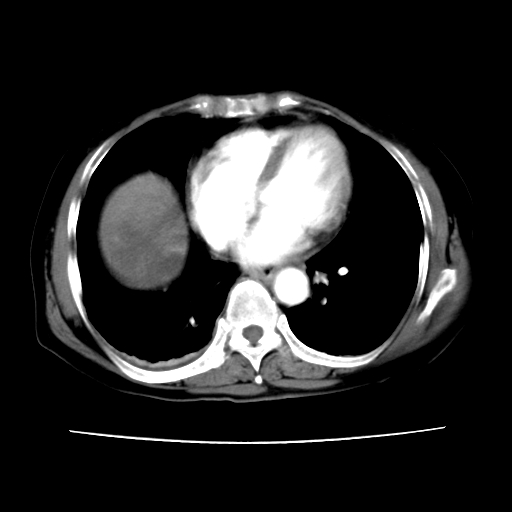

ct增强

6月份ct片显示肝内巨大混杂密度团块,伴包膜下积液(内含液液平面),增强多无明显强化。只能考虑肝占位病变,并肝内、血膜下血肿。肝ca并出血多见,而肝血管瘤并破裂出血少见。

6月份ct片显示肝内巨大混杂密度团块,伴包膜下积液(内含液液平面),增强多无明显强化。只能考虑肝占位病变,并肝内、包膜下血肿。肝ca并出血多见,而肝血管瘤并破裂出血少见。

考虑肝腺瘤出血可能,肝血管瘤增强表现不是很典型,放在第二。

考虑为肝血管瘤破裂出血并肝包膜下血肿;右侧少量胸腔积液。